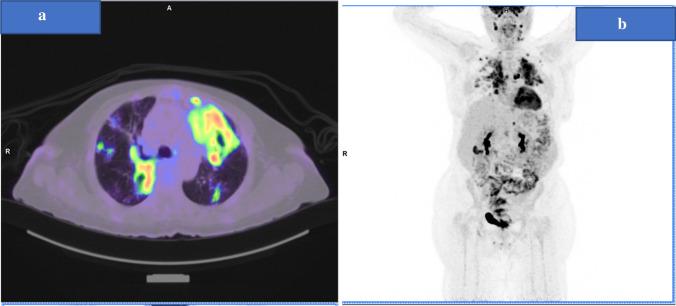

Immune checkpoint inhibitors (ICIs)-anti-programmed death-1 (PD-1) and their ligands (PD-L1 and PD-L2) have become widely used in the treatment of several malignancies. Many immune-related adverse events (irAEs) have been linked to these agents. Nonetheless, tuberculosis (TB) reactivation during their use is increasingly recognized and reported. Herein, we present a 58-year-old lady with advanced non-small cell lung cancer (NSCLC) ALK-negative, EGFR wild, and PD-L1 immune histochemistry (IHC) strongly positive in 95% of tumor cells, on ongoing treatment with Pembrolizumab as a first-line monotherapy. Our patient presented with 1-week history of productive cough and high-grade fever. Further workup yielded the diagnosis of pulmonary tuberculosis after her Pembrolizumab sixth cycle with positive AFB smear and TB PCR from BAL (rifampin resistance not detected), with negative HIV status. Hence, immunotherapy was held, and patient was commenced on anti-TB regimen. History revealed contact with active TB patient over the past decade, without previous documentation of latent TB or previous TB infection. Her sputum AFB smear remained persistently positive 4 weeks through anti-TB regimen course. Later, the patient was discharged after her sputum was cleared from AFB (two negative sets). In light of pembrolizumab mechanism of action as an immune checkpoint inhibitor, we suspected its implication on reactivating latent TB which was observed in our patient demonstrating features of pulmonary tuberculosis. She was not re-challenged with Pembrolizumab following TB diagnosis.

免疫检查点抑制剂(ICIs)-抗程序性死亡受体-1(PD-1)及其配体(PD-L1 和 PD-L2)已广泛用于治疗多种恶性肿瘤。许多与免疫相关的不良反应(irAEs)与这些药物有关。尽管如此,在使用这些药物期间,结核病(TB)的再激活越来越受到关注和报道。在此,我们报告了一例 58 岁的晚期非小细胞肺癌(NSCLC)ALK 阴性、EGFR 野生型和 PD-L1 免疫组织化学(IHC)强阳性(肿瘤细胞中 95%阳性)的患者,正在接受 Pembrolizumab 作为一线单药治疗。该患者在接受 Pembrolizumab 第六个周期后出现了 1 周的有痰咳嗽和高热病史。进一步的检查在她的 BAL 中发现了 AFB 涂片阳性和 TB PCR 阳性(未检测到利福平耐药),同时 HIV 检测为阴性,最终诊断为肺结核。因此,停止了免疫治疗,并开始了抗结核治疗方案。患者有过去十年接触活动性结核患者的病史,但没有潜伏性结核或既往结核感染的记录。她的痰 AFB 涂片在抗结核治疗方案的 4 周内持续阳性。在经过两个疗程的抗结核治疗后,她的痰 AFB 转为阴性。随后,患者在痰中清除 AFB(两次阴性)后出院。鉴于 Pembrolizumab 作为免疫检查点抑制剂的作用机制,我们怀疑其在激活潜伏性 TB 方面的作用,这在我们的患者中表现为肺结核的特征。在诊断为结核病后,该患者未再接受 Pembrolizumab 治疗。